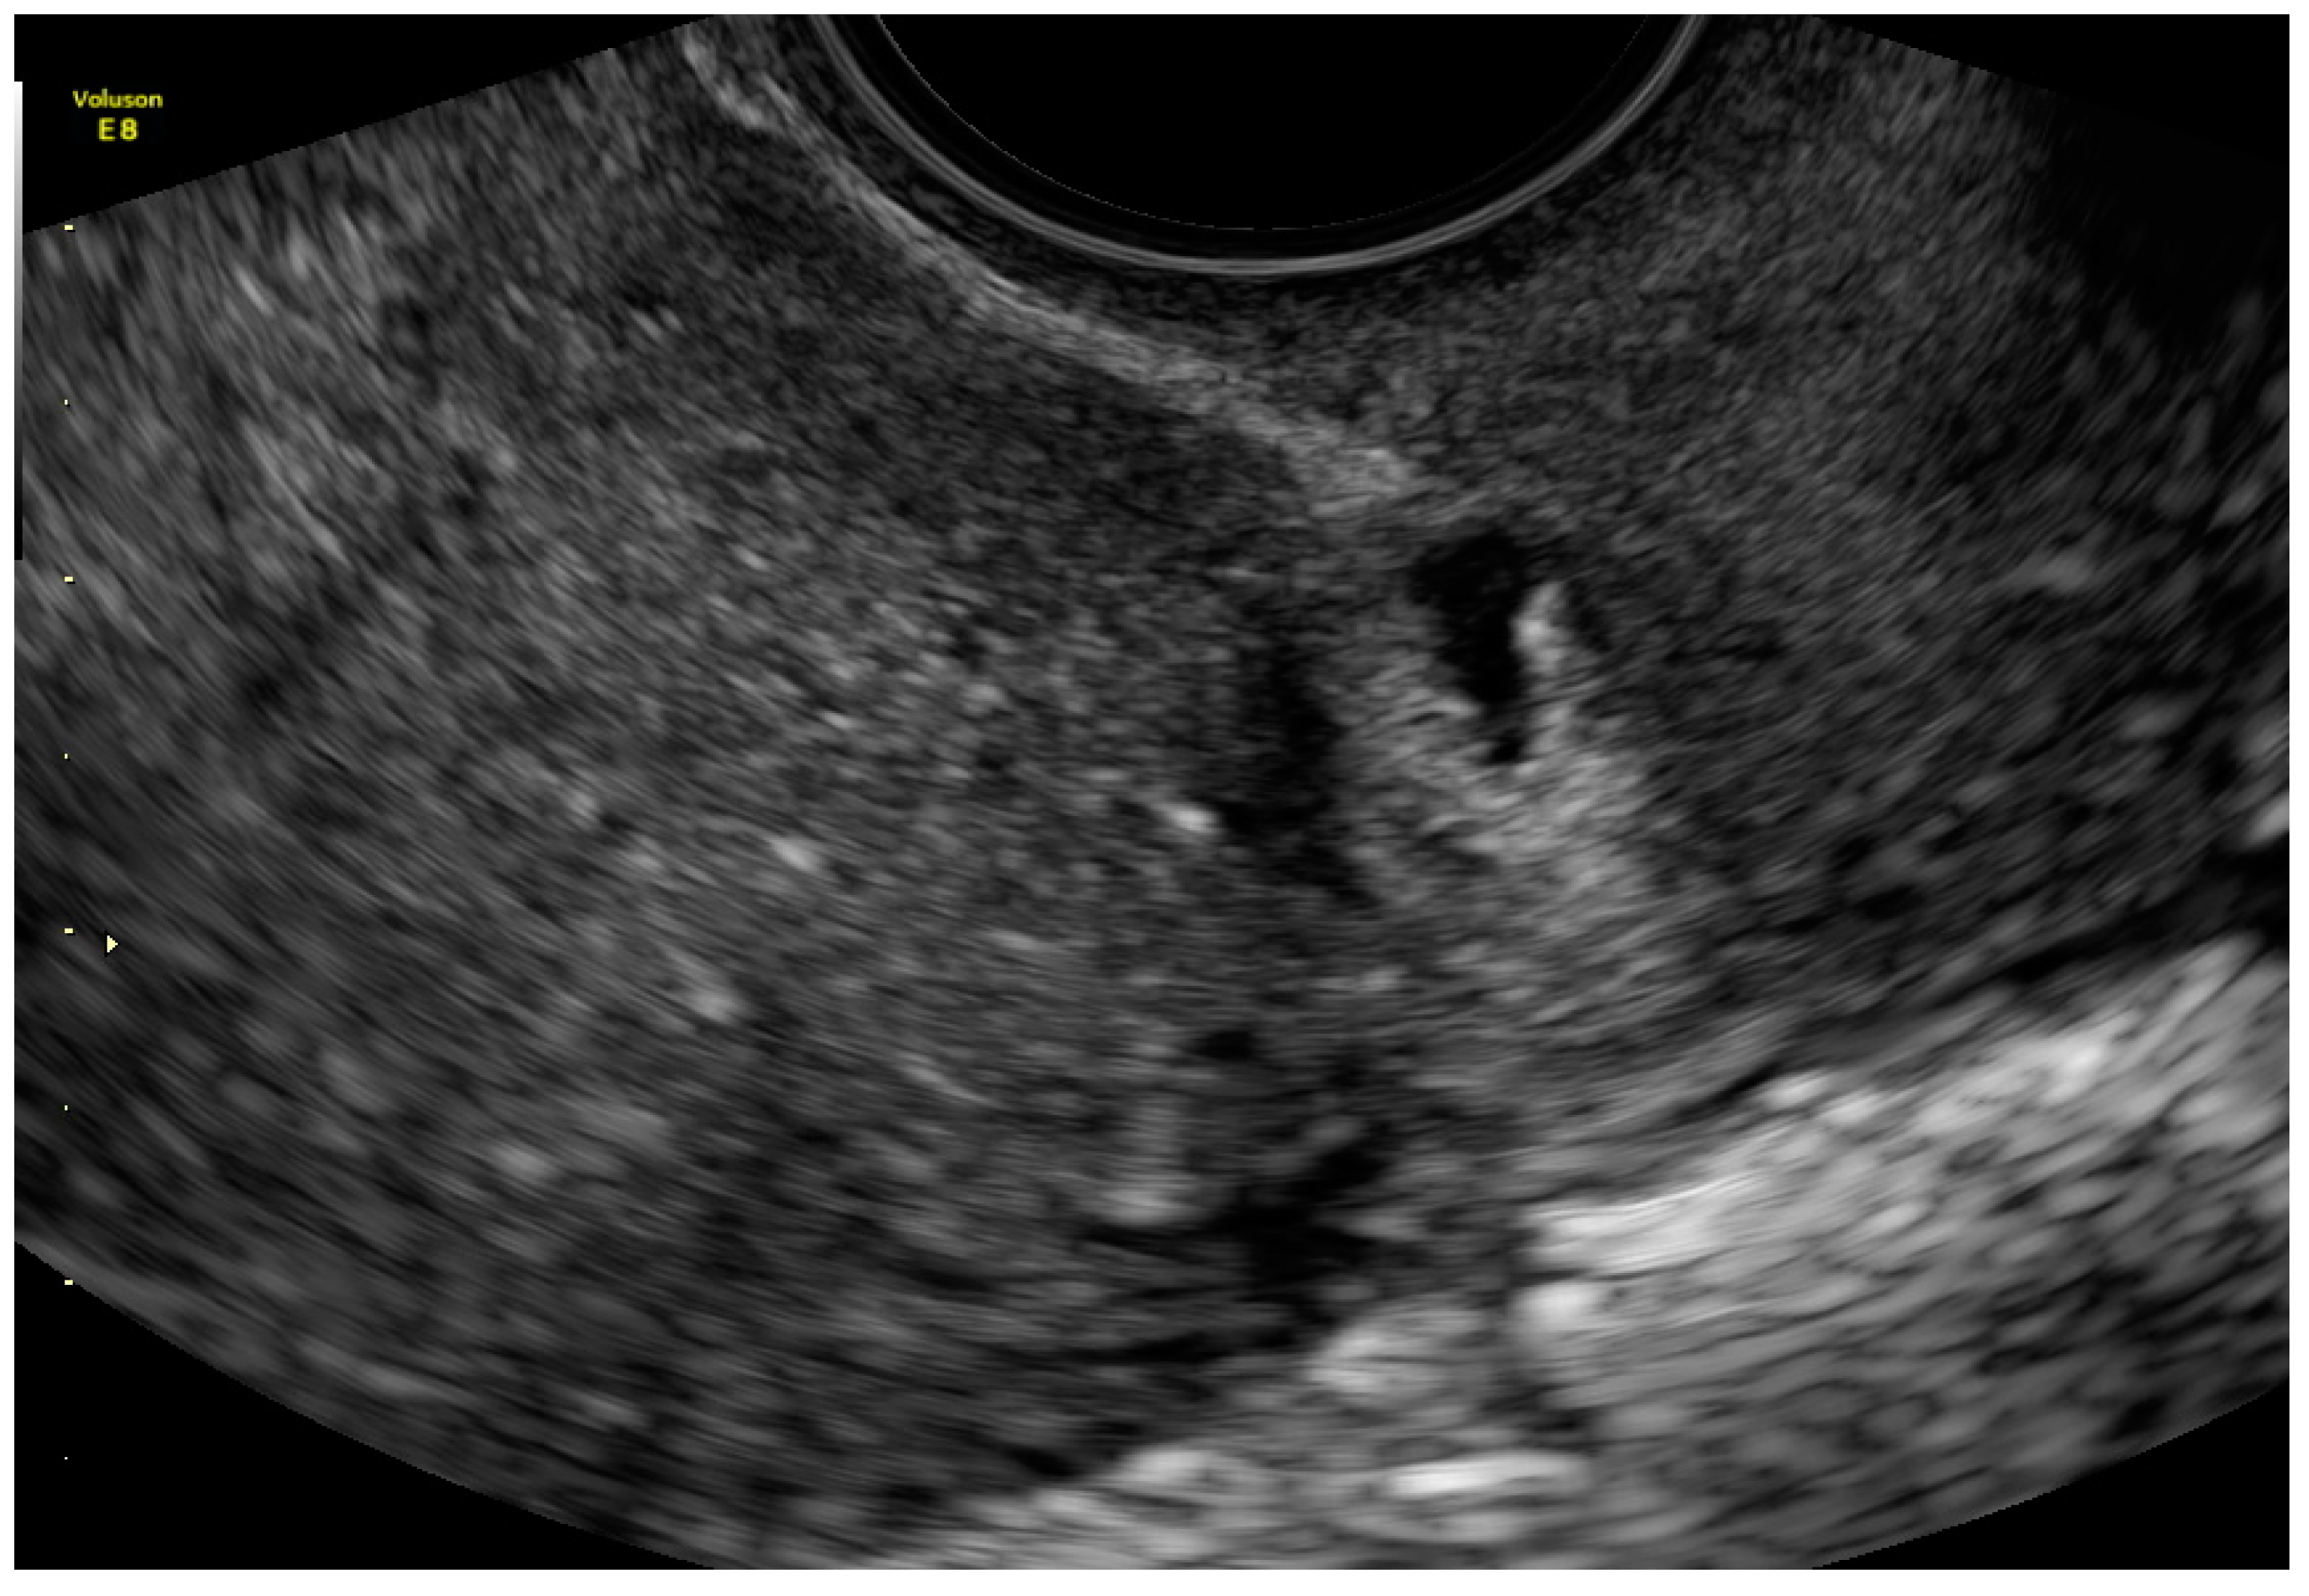

- 1

- an empty uterine cavity with clear endometrium and empty endocervical canal,

- 2

- the detection of a gestational sac within the anterior lower segment of the uterus embedded in the cesarean scar,

- 3

- an absent or thin (<5 mm) myometrium layer between the gestational sac and the bladder,

- 4

- 5

- the pathologies of the adnexa should be excluded, and there should be no detection of fluid in the Douglas pouch unless in the case of a massive hemorrhage or rupture of the uterus [5].